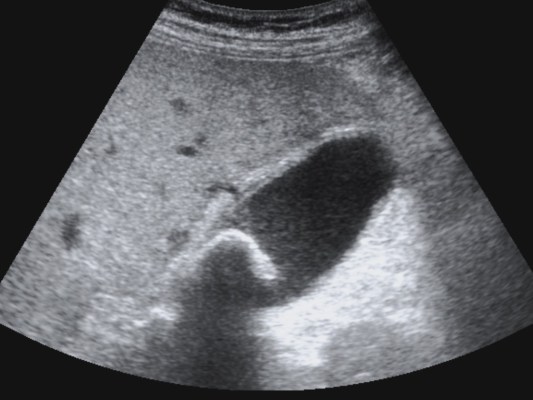

Se realiza ecografía abdominal:

Con estos hallazgos ecográficos podemos concluir que el paciente presenta una COLECISTITIS AGUDA.

Es la técnica de elección para el diagnóstico cuando se sospecha colecistitis (S y E > 95%, Robert et al.).

Criterios ecográficos de colecistitis (No existe consenso generalizado):

– Murphy ecográfico positivo y colelitiasis: es la combinación de signos ecográficos más predictiva de colecistitis aguda (VPP 92%). Puede resultar difícil observa la litiasis si ésta se localiza en el conducto cístico o en el cuello de la vesícula. Con engrosamiento mural el VPP aumenta al 94%)

– Otros signos secundarios son:

- Engrosamiento de la pared vesicular (>4mm) en ausencia de enfermedad hepática crónica, ascitis o insuficiencia cardiaca (el VPP asciende al 94%).

- Líquido perivesicular.

- Imágen de triple pared con capa hipoecoica central.

- Vesícula biliar distendida.

- Presencia de barro o material ecogénico en el interior de la vesícula.

Según la guía de Tokyo, el diagnóstico de colecistitis litiásica aguda puede hacerse cuando están presentes al mismo tiempo los siguientes hallazgos: engrosamiento de la pared vesicular mayor de 5 mm, líquido pericolecístico y Murphy ecográfico positivo. Otros signos son distensión vesicular, litiasis biliar, barro o material ecogénico biliar y gas en la pared. Sin embargo, debido a diferencias entre datos de frecuencia de sensibilidad y especificidad de los hallazgos individuales, el diagnóstico debe ser hecho a partir del análisis juicioso de los hallazgos individuales.